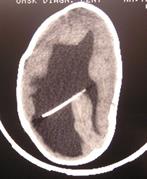

Рис.38. КТ-граммы ребенка с гидроцефалией тяжелой степени, ЛКИ=53%,

после операции нормализация внутричерепных взаимоотношений, ЛКИ= 3,2%.